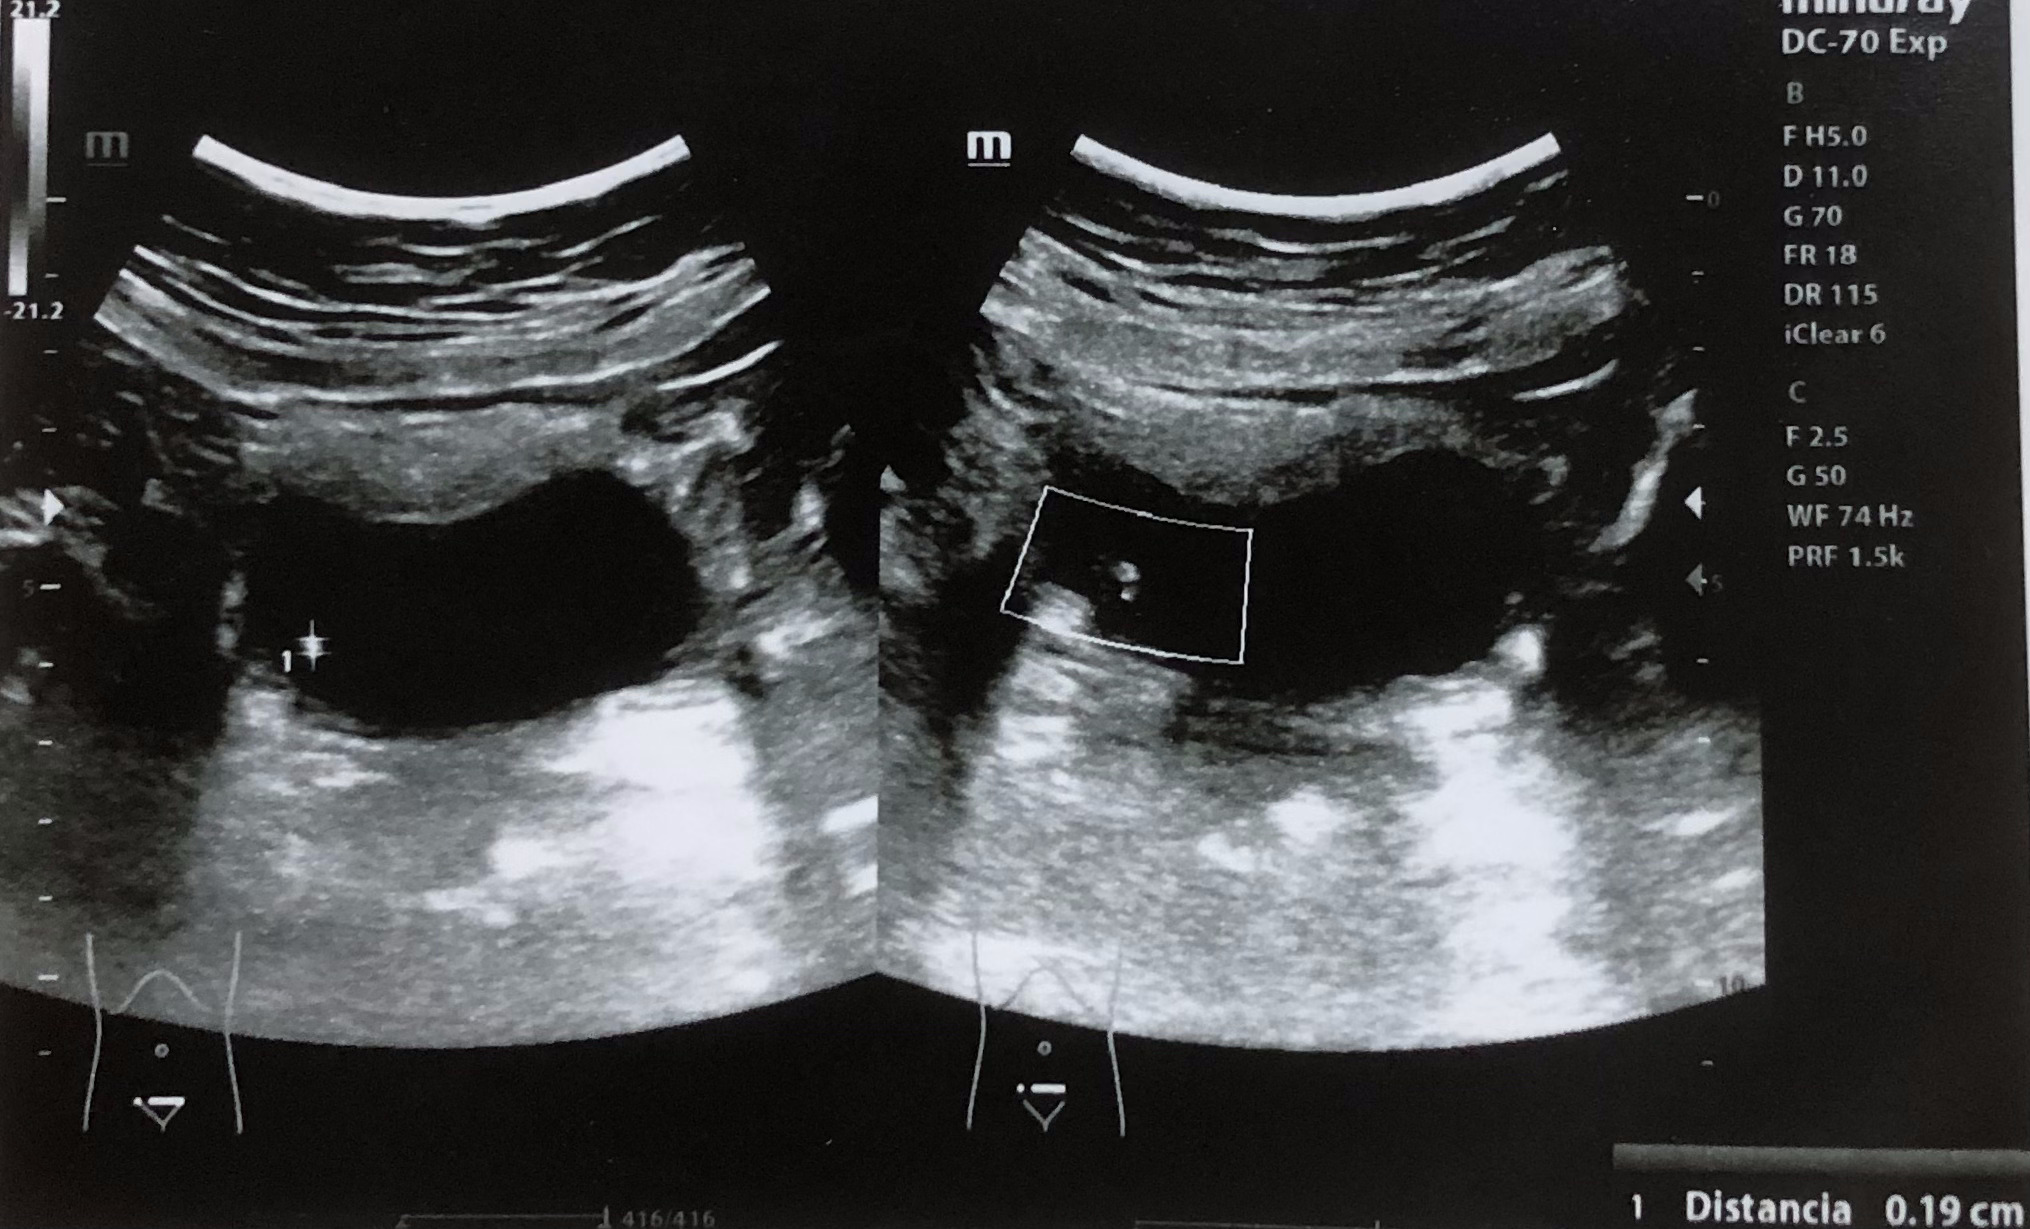

Se realiza ecografía renal donde se aprecia lesión hiperecogénica redondeada en pared inferior derecha de vejiga sin sombra posterior de 0,7 x 0,61 cm, que no se moviliza con cambios posturales de la paciente. Centelleo dudoso.